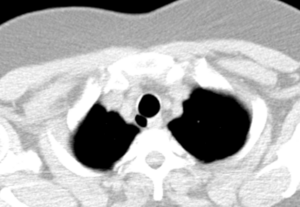

CT scan of the thorax (axial lung window)

Structure

An adult's trachea has an inner diameter of about 1.5 إلى 2 سنتيمتر (1⁄2 إلى 3⁄4 in) and a length of about 10 إلى 11 cm (4 إلى 4+1⁄4 in), wider in males than females.[1] The trachea begins at the lower edge of the cricoid cartilage of the larynx[2] at the level of sixth cervical vertebra (C6)[1] and ends at the carina, the point where the trachea branches into left and right main bronchi.,[1] at the level of the fourth thoracic vertebra (T4),[1] although its position may change with breathing.[2] The trachea is surrounded by 16–20 rings of hyaline cartilage; these 'rings' are 4 millimetres high in the adult, incomplete and C-shaped.[1] Ligaments connect the rings.[2] The trachealis muscle connects the ends of the incomplete rings and runs along the back wall of the trachea.[2] Also adventitia, which is the outermost layer of connective tissue that surrounds the hyaline cartilage, contributes to the trachea's ability to bend and stretch with movement.[3]

Although trachea is a midline structure, it can be displaced normally to the right by the aortic arch.[4]